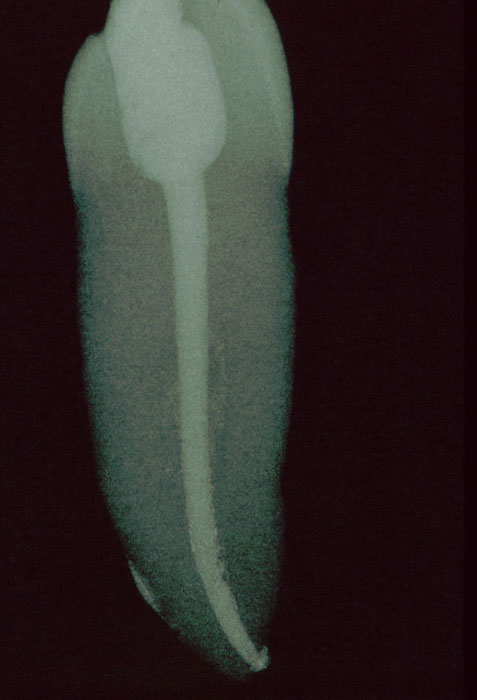

Röntgenkontrolle nach Obturation

Ausschließlich Sealer (AH plus) ist lingual durch den Frakturspalt

ausgetreten. Auf Höhe der Fraktur deutet eingeflossener Sealer darauf hin,

dass sich die Fraktur bis in die labiale Seite der Wurzel erstreckt.

Akzessorische, lingual und labial lokalisierte Hohlräume sind durch Sealer

und auch etwas Guttapercha dargestellt aber nicht dicht gefüllt, während

die Guttaperchafüllung des präparierten Wurzelkanals dicht erscheint.